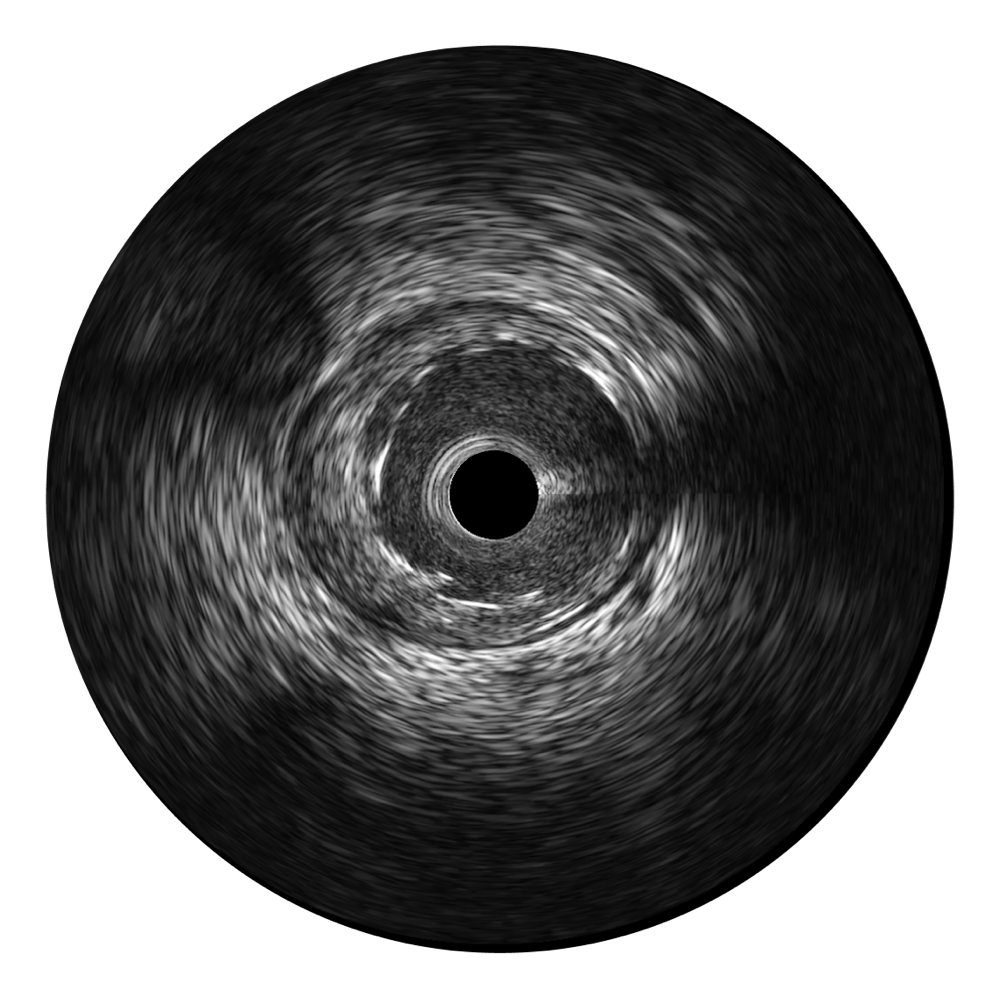

開(kāi)立寬頻IVUS圖像

傳統(tǒng)IVUS圖像

對(duì)比傳統(tǒng)IVUS導(dǎo)管成像,開(kāi)立寬頻IVUS圖像的近場(chǎng)支架梁顯影更細(xì)膩,遠(yuǎn)場(chǎng)中膜外血管仍清晰可辨,兼顧遠(yuǎn)中近,兼顧分辨力與穿透深度